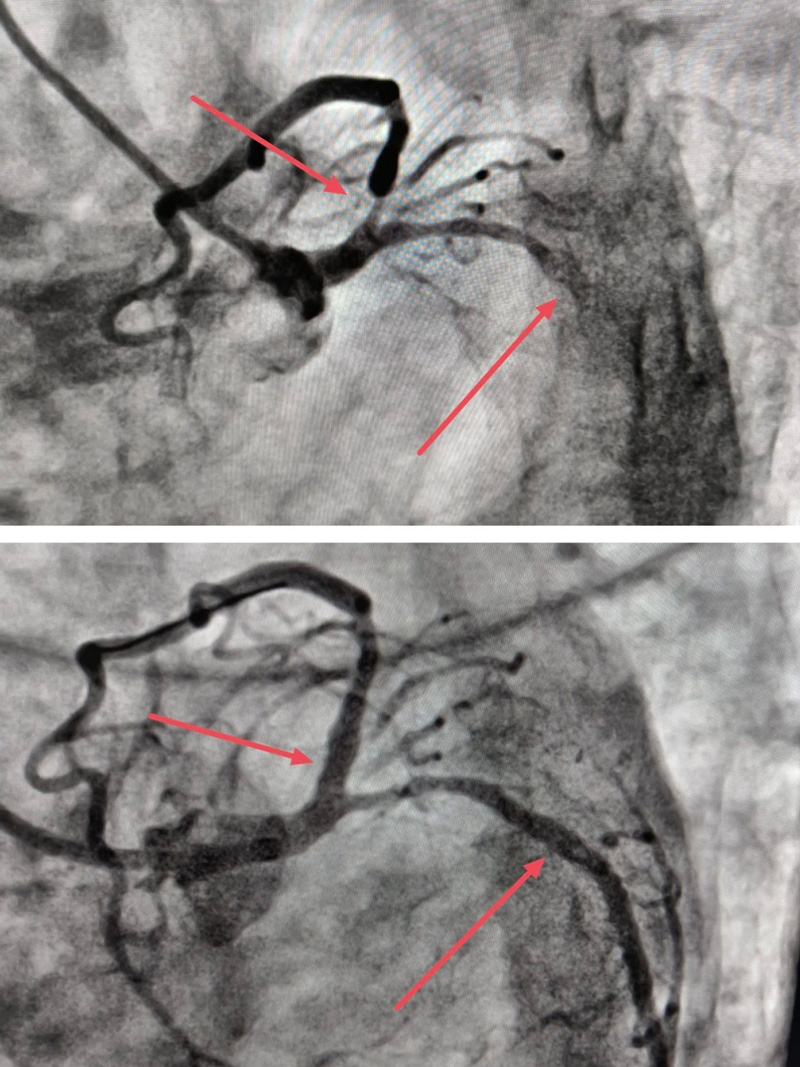

来凤县人民医院心血管内科首次开展IVUS(血管内超声)指导下冠脉复杂介入治疗,并顺利完成2例IVUS指导下精准支架植入术。

3月15日,来凤县人民医院副院长张承中、心血管内科主任朱兴彪及介入团队其他成员,全面评估患者病情后,决定在IVUS的指导下,精准植入支架——球囊扩张、IVUS检查、支架植入、复查IVUS,整个手术不到两小时,复查IVUS和造影结果非常满意,患者无任何不适。

据了解,来凤县人民医院导管室成立3年以来,手术量逐渐增加,遇到高危、复杂病变也越来越多,在高危、复杂的冠脉病变介入手术中,需要对病变位置、程度、累及范围等进行精确判断,而仅靠冠脉造影,并不能让医生精确掌握血管病变情况,怎么办?不用担心!被称为心血管介入医生的“天眼”的IVUS(血管内超声)来帮忙啦!

IVUS(血管内超声)是通过导管技术将微型超声探头送入血管腔内,显示血管横截面图像,从而提供在体血管腔内影像的一种技术。与冠脉造影只能对血管内血流情况进行成像,且容易受造影角度的影响,无法对血管壁上的斑块发展情况进行判断相比,IVUS能够精确测定管腔、血管直径以及判断病变严重程度及性质,在提高对冠状动脉病变的认识和指导介入治疗方面起了非常重要的作用。